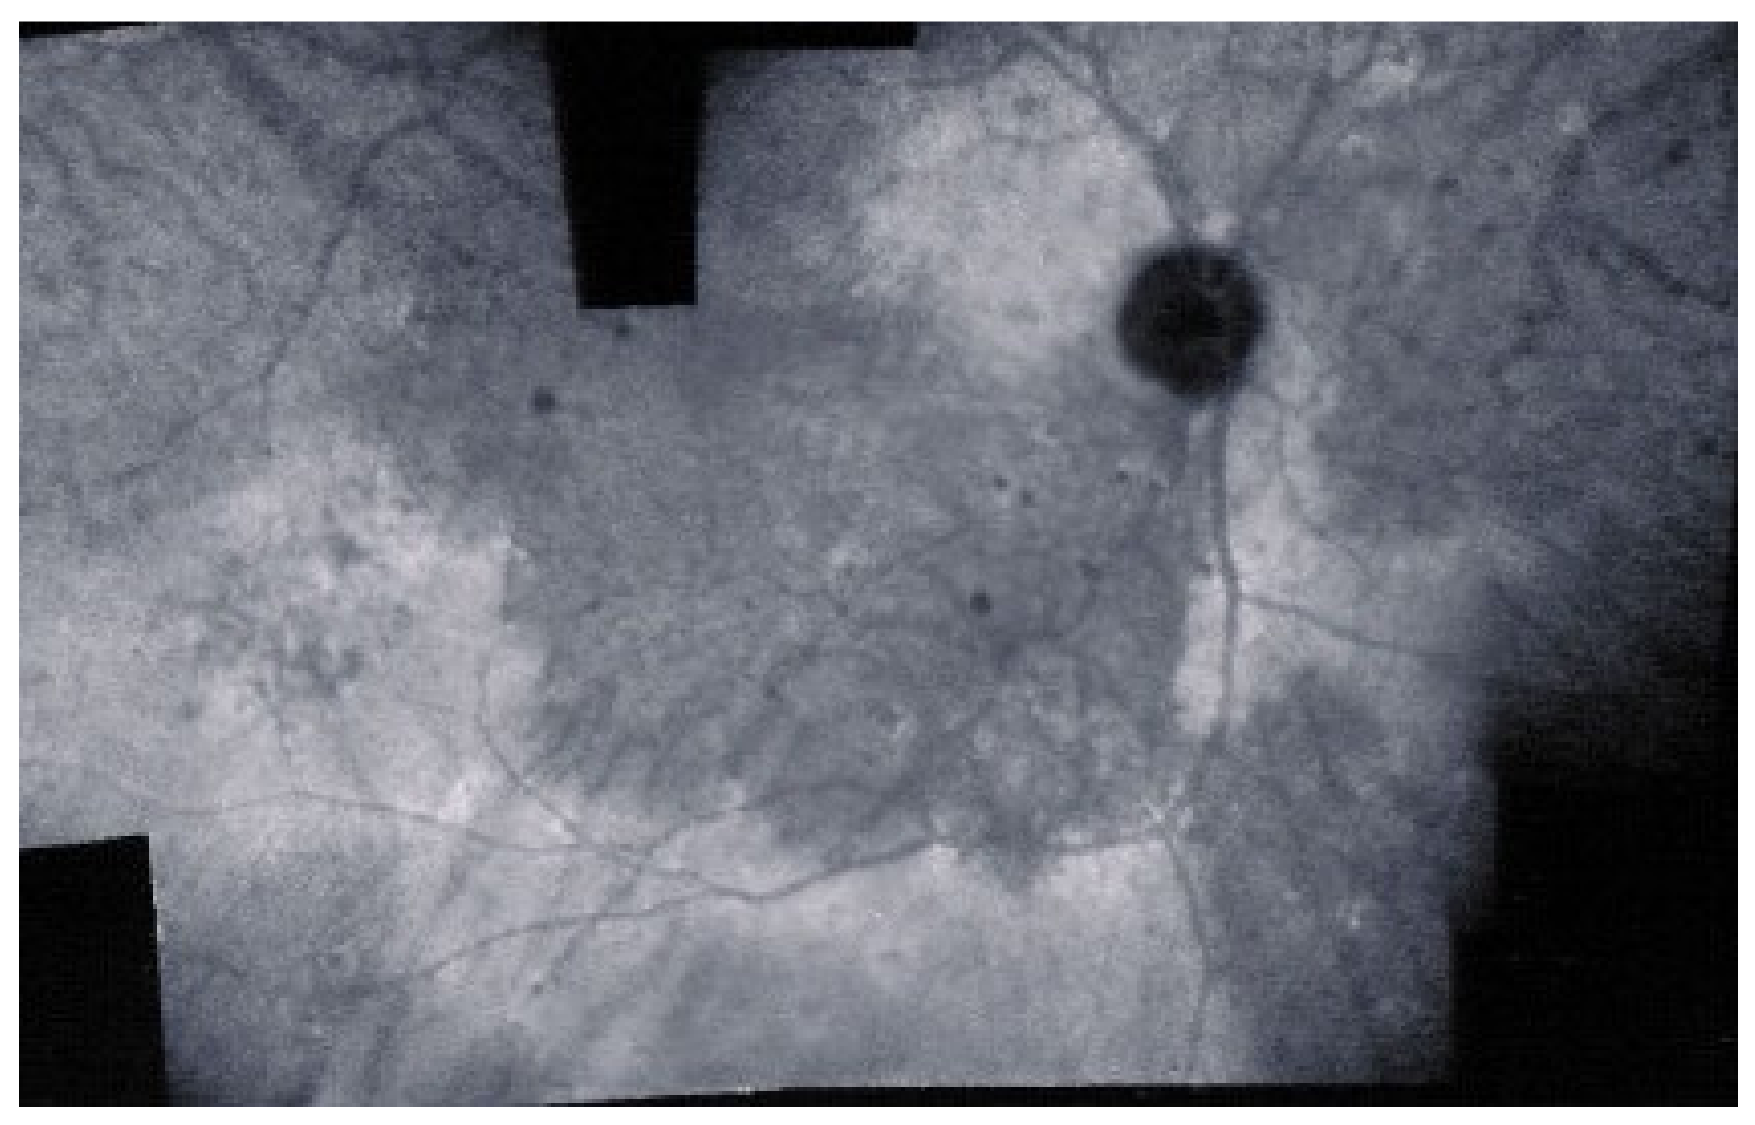

As for all PICCPs, multimodal imaging is best accounting for MFC features (Table 4). On ICGA, the first set of signs identifies old scarred chorioretinal lesions and consists of hypofluorescent areas persisting up to the late angiographic phase, distributed at random in the fundus, corresponding to late hyperfluorescence on FA, typical for chorioretinal atrophy from scars of previous inflammatory episodes seen on colour fundus photos. The second set of signs can be seen in addition to the previously described signs when choroiditis recurs or can be seen in the absence of scars when it is the first episode. The signs consist of hypofluorescent areas, either silent on fluorescein angiography or hyperfluorescent in the late phase and usually not visible on fundus examination, representing areas of new inflammatory involvement (Figure 14). As in many PICCPs, some cases may present peripapillary hypofluorescence, translating functionally into an enlarged blind spot [18,36,54,55] (Figure 15). The hypofluorescent areas can completely regress if inflammation suppressive treatment is started promptly. In a substantial proportion of cases, the extent of ICGA hypofluorescence reflecting choriocapillaris hypoperfusion or nonperfusion is far more widespread than visible lesions let suspect, showing widespread areas of late occult hypofluorescence with absolutely no signs visible on fundus examination or on fluorescein angiography (Figure 15).

Figure 15.

Vast areas of ICGA hypofluorescence indicating choriocapillaris hypo or nonperfusion surrounding the disc. These areas indicate that in some cases, the inflammatory process going on sub-clinically is involving vast areas of choriocapillaris perfusion problems and can be a trigger for the development of CNVs.